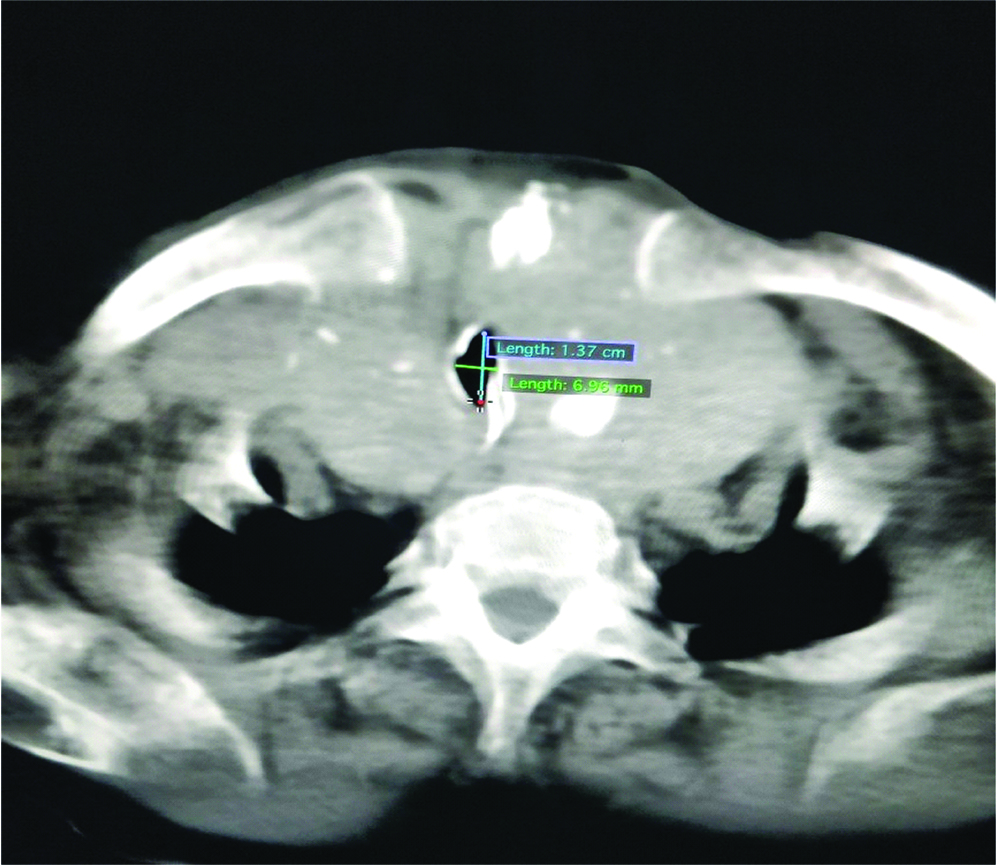

On examination, vitals were stable with PR-70/min, BP-140/90 mm Hg, SpO2 of 100%. Baseline investigations were within normal limits with Hb-10.9 mg/dL and low calcium 7.3 mg/dL. Electrocardiogram (ECG) showed complete right bundle branch block with normal Echocardiography (ECHO) study. Thyroid profile showed low TSH-0.011 IU/mL with normal T3, T4 values. Chest radiograph showed narrowed and deviated trachea with widening of superior mediastinum [Table/Fig-2]. Computed Tomography (CT) neck showed thyroid gland with heterogeneous enhancement with areas of necrosis and calcifications within the gland. The right lobe measured 10.8x5.5 cm and left lobe measured 8.9x5 cm. Inferiorly left lobe was seen extending into retrosternal area. Superiorly, the right lobe was extending upto C2 vertebra. Medially the lesion was compressing trachea with significant narrowing of air column with subglottic diameter of 6.2 mm [Table/Fig-3]. Upper trachea was displaced to left side. The lesion was abutting thyroid, cricoid cartilages and inferiorly arch of aorta. Fine Needle Aspiration Cytology (FNAC) report was consistent with benign follicular nodule.

CT scan of neck showing narrowed trachea.